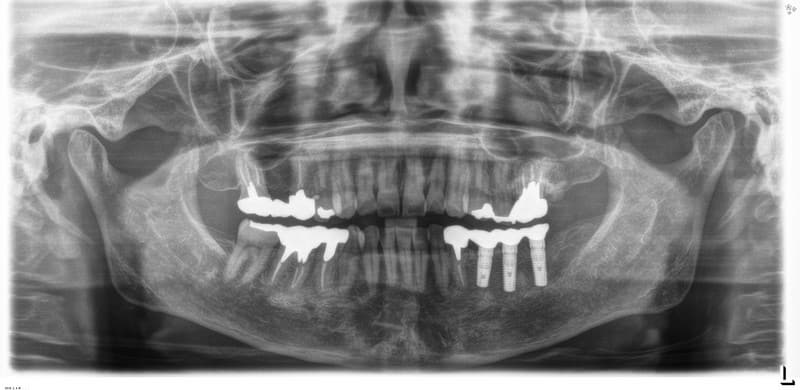

技工士さんがあなただけの人工の歯をカスタムメイドで製作します。

人工の歯をインプラントに連結して完成となります。